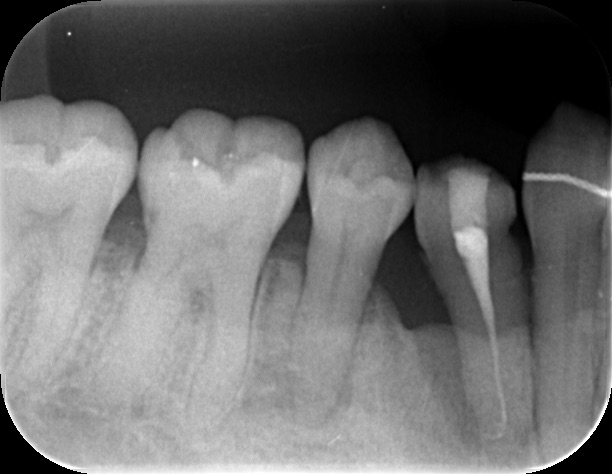

根管処置後、歯槽骨の回復を待つ。この時点では歯の動揺はかなりあり、抜けてしまうんではないかと思うぐらい。

感染が取れ、過度な咬合力がかからなければ歯槽骨も回復してくる。動揺もなくなる。